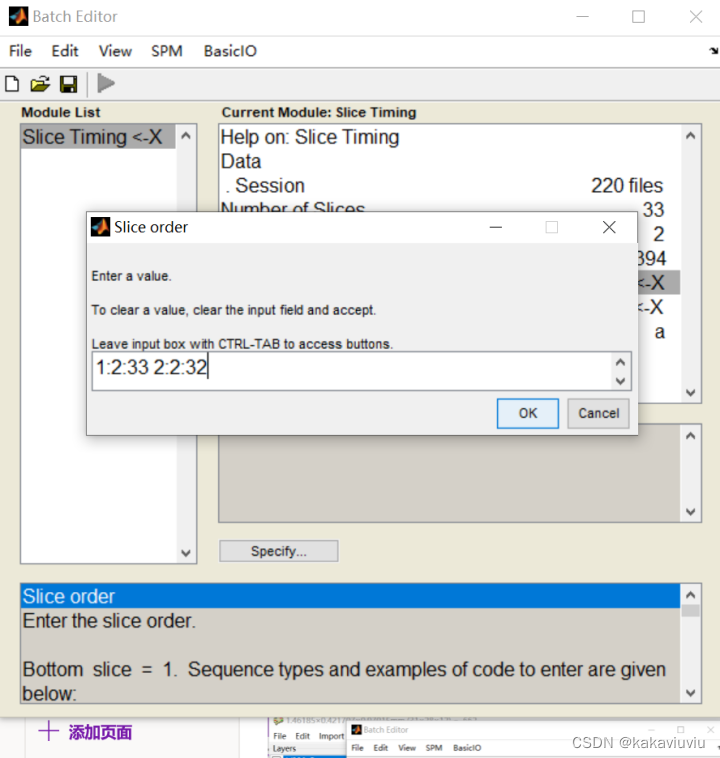

扫描顺序:1是首项,2是步长,33是尾项;两个等差数列之间用空格隔开(会自动判断是否结束)。翻译过来就是1 3 5 7层 ... 2 4 6 8层...这样的扫描顺序